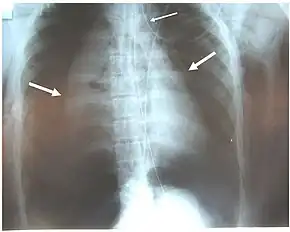

Pneumothoraces of both lungs (large arrows), pneumomediastinum (small arrow) and subcutaneous emphysema in a patient with complete disruption of the right bronchus. Air leak was continual despite suction.[1]

Damage to the airways can cause subcutaneous emphysema (air trapped in the subcutaneous tissue of the skin) in the abdomen, chest, neck, and head.[2] Subcutaneous emphysema, present in up to 85% of people with TBI,[10] is particularly indicative of the injury when it is only in the neck.[13] Air is trapped in the chest cavity outside the lungs (pneumothorax) in about 70% of TBI.[4][10] Especially strong evidence that TBI has occurred is failure of a pneumothorax to resolve even when a chest tube is placed to rid the chest cavity of the air; it shows that air is continually leaking into the chest cavity from the site of the tear.[11] Air can also be trapped in the mediastinum, the center of the chest cavity (pneumomediastinum).[4] If air escapes from a penetrating injury to the neck, a definite diagnosis of TBI can be made.[10] Hamman's sign, a sound of crackling that occurs in time with the heartbeat, may also accompany TBI.[14]